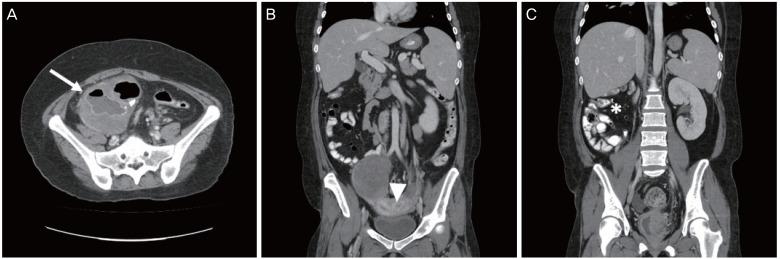

Müllerian anomalies are rare deformities in women, and only a few cases concerning gynecologic malignancies arising in patients with congenital uterine malformations have been reported. Herein, we present the case of a 34-year-old woman with dysgerminoma with a Müllerian anomaly (uterus didelphys). She had secondary amenorrhea, and an ovarian mass and uterus didelphys were discovered during examination. After right salpingo-oophorectomy, the tumor was confirmed as dysgerminoma, and a chromosome study revealed a normal female karyotype (46, XX). The patient completely responded to 6 cycles of chemotherapy. To our knowledge, this is the first reported case of dysgerminoma with uterus didelphys. Although gynecologic malignancies in patients with Müllerian anomalies are very rare, clinicians should be aware of the coexistence of gynecologic malignancies and uterine malformations.

苗勒管异常在女性中较为罕见,仅有少数关于先天性子宫畸形患者发生妇科恶性肿瘤的病例报道。在此,我们报告一例34岁患有无性细胞瘤合并苗勒管异常(双子宫)的女性病例。她出现继发性闭经,检查时发现卵巢肿块和双子宫。右侧输卵管卵巢切除术后,肿瘤被确诊为无性细胞瘤,染色体研究显示为正常女性核型(46, XX)。该患者对6个周期的化疗完全缓解。据我们所知,这是首例双子宫合并无性细胞瘤的报道病例。尽管苗勒管异常患者发生妇科恶性肿瘤非常罕见,但临床医生应意识到妇科恶性肿瘤与子宫畸形可能并存。